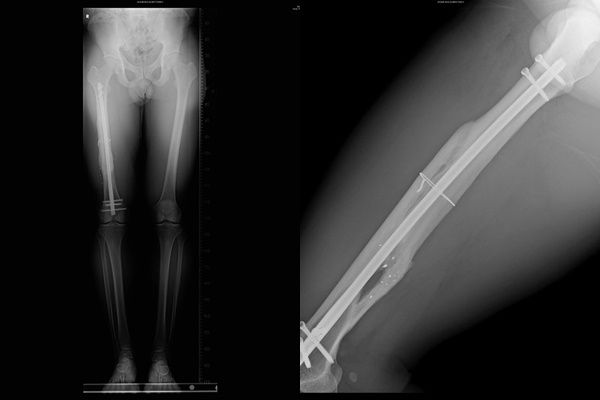

▲裡面留下很多子彈碎片。(圖/翻攝自館長臉書)

館長稍早在臉書發文提到,「今天是我中槍滿兩年了,回到醫院照片子檢查,雖然天天腳都會痛,但是我還是堅持訓練,反正腿傷問題是無解,命有救回來就好,看裡面還留一堆子彈碎片,就當作是給我自己的紀念品吧。」

當時,館長右手臂一發槍擊穿透傷,子彈貫穿手臂後再擊中右大腿,另右大腿也粉碎性骨折,彈頭卡在腿內,而右小腿則中了一槍,且彈頭卡在腳踝中。